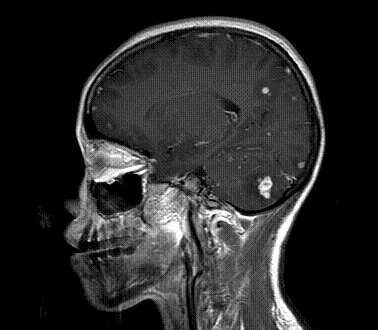

以下是引用xly在2009-5-20 11:38:00的发言:[br]大脑、小脑及脑干多发结节状及环状稍长t1、长t2异常信号影,部份病灶中心见稍短t1、短t2信号,病灶边缘光滑、边界清楚,灶周环状水肿,dwi为低信号,增强扫描上述病灶均匀强化,部份病灶中心无强化,脑膜小结节异常强化,考虑脑膜脑结核可能性大。胸片如何?ppd如何?期待结果。